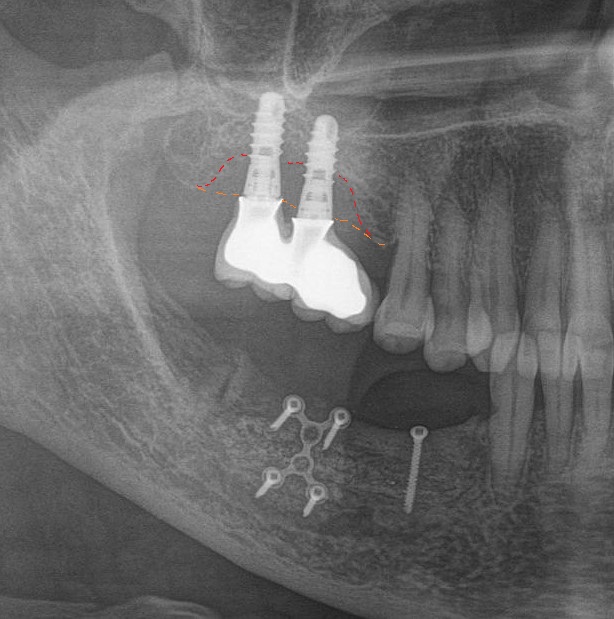

Дальше на очереди гуру планирования и расчетов.

Сразу ясно: что-то тут не так. Пациент был лишен 6-ого и 7-ого зуба на верхней челюсти справа. Но хирург почему-то установил имплантаты в проекции зубов 7 и 8. В связи с этим доктору-ортопеду и зубному технику пришлось извращаться и изготавливать вот такой ущербный мостовидный протез. Такая причудливая форма способствует забиванию и скоплению пищи под этим навесом. Именно это, собственно, и привело к критичной убыли костной ткани вокруг имплантатов.

Это чудо необходимо демонтировать и начинать сношаться с проблемой отсутствия зубов заново. Писать о том, что ценник в связи с этим подлетает до небес, думаю, не стоит. Не так ли? Ведь в переделку входят:

Тут представлена ошибка, как в позиционировании иплантата, так и в изготовлении вот такого великолепного мостовидного протеза.

Кроме уже известной нам цементной фиксации, с выведением материала под десну, меня добила форма этой конструкции. Она идеальна для того, чтобы под протез забивалась пища и хранилась там годами.

На самом деле, если бы был изготовлен мост адекватной формы, без нависающих краев, с хорошей промывной частью и винтовой фиксацией, то можно было бы избежать этой проблемы.

Но с другой стороны, если бы хирург правильно спозиционировал имплантаты, можно было бы изготовить коронки на каждый зуб по отдельности и не извращаться с мостовидным протезом. Это упрощает гигиену и уход за ортопедическими конструкциями.